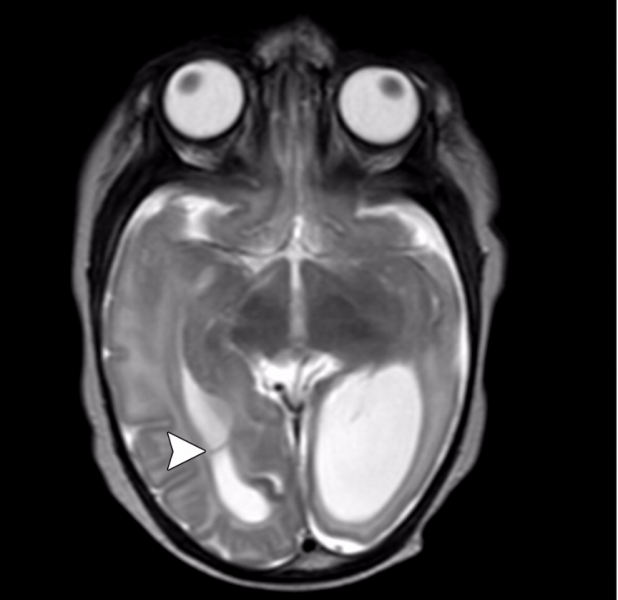

In an analysis that included more than 1.4 million births, exposure to magnetic resonance imaging (MRI) during the first trimester of pregnancy compared with nonexposure was not associated with increased risk of harm to the fetus or in early childhood.